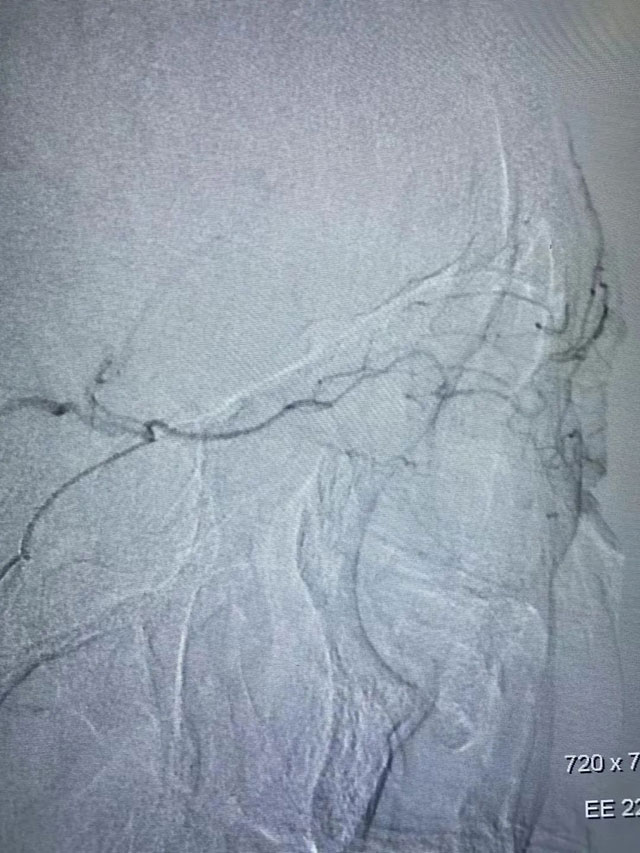

前些时候贾老先生右眼突发失明5小时,在家属陪同下,前来东方总院急诊科,1月24日晚上接到急诊会诊后,被诊断为:眼动脉栓塞导致眼动脉急性缺血引发的突发性失明,俗称“眼卒中”。黄旭东院长得知贾先生已经失明5小时了,而经皮眼动脉溶栓治疗最佳手术时间是失明后6小时以内,情况十分紧急!时间越久,失明风险越大,看着贾先生家属焦急的脸,黄院长当机立断,立即紧急启动眼动脉溶栓治疗绿色通道,为贾先生量身定制了手术方案。当天晚上,黄旭东介入团队放弃了晚上休息时间,在导管室老师们的配合帮助下,进行术前介入溶栓准备,为贾先生进行了手术。

目前,国内针对“眼卒中”主要是采取动脉顺行眼动脉介入溶栓治疗,最佳治疗时间是6小时以内,且顺行眼动脉介入溶栓经脑血管,路径长、风险大,容易造成脑出血、脑梗等问题。而贾先生的手术历时仅1个小时,就顺利完成。术后,贾先生睁开眼睛第一句话就是:“我又能看见啦!淮南东方医院介入科的专家就是厉害!”目前,贾先生视力已恢复到眼前50cm指数。

“脑卒中是大家熟知的一种疾病,对于脑卒中的常见症状和预防措施了解的也比较多,而眼卒中就相对比较陌生。”介入科医疗中心黄旭东院长介绍说:“正如脑部血液阻塞会导致卒中一样,视网膜血管急性阻塞也会导致眼部卒中,这种疾病发病急、病情重、会突然导致视力丧失,治疗不及时的话会有很大概率导致永久失明。”目前眼卒中的首选治疗方式就是溶栓治疗,东方医院集团介入科医疗中心此次眼动脉造影+溶栓术治疗眼动脉急性栓塞手术作为淮南首例,填补了此项目在当地医疗技术上的空白。